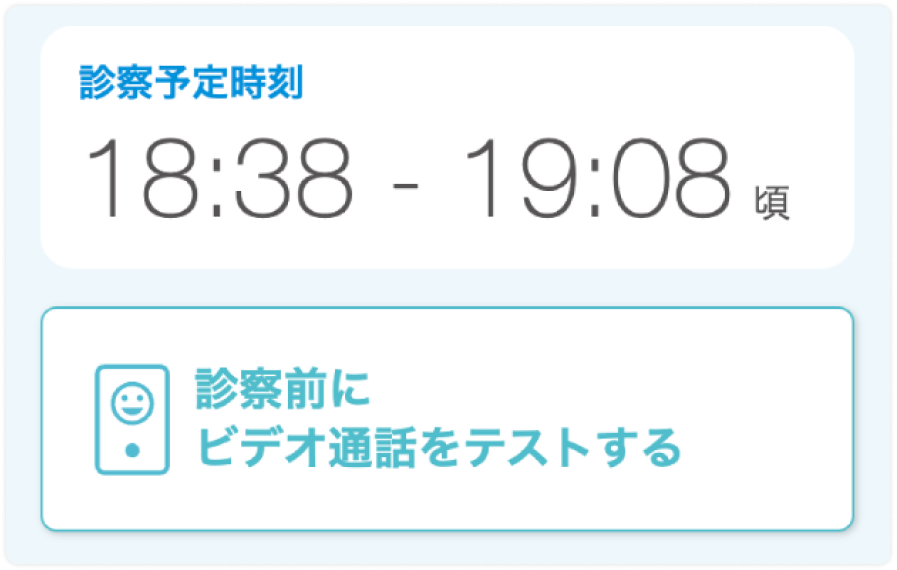

診察までの手順

ビデオ通話の準備

STEP1

お申し込み完了後、SMSにマイページのURLが届きます

STEP2

マイページで保険証と支払い方法を登録します

STEP3

ビデオ通話が正常に使えるかテストします

うまく表示されない場合は下記ページにしたがって機器の設定をお願いいたします。

STEP4

診察時間になるとビデオ通話開始ボタンが表示されます

処方できるお薬の例 - 診察の流れ(ビデオ通話の使い方)はどうなりますか?お申し込みが完了しますとマイページのURLがSMS(ショートメッセージ)にて届きます。

診察開始前の待ち時間に、マイページ内で保険証・お支払い方法をご登録ください。

詳しくは下記をご参照下さい。

診察までの手順(ビデオ通話の準備)